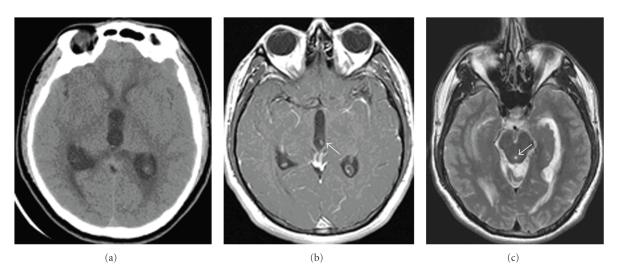

Neurocysticercosis is endemic in the developing world, but is becoming more common in the US due to immigration. A 24-year-old man presented with acute hydrocephalus and headaches, nausea, and vomiting. Head CT revealed a 3rd ventricular cyst and immunological studies were suggestive of neurocysticercosis. EVD placement resulted in migration of the cyst interiorly and superiorly with return of normal CSF flow by MRI and resolution of symptoms. Review of this condition is important given increasing incidence in the United States.

神经囊尾蚴病在发展中国家呈地方性流行,但由于移民因素,在美国正变得越来越常见。一名24岁男性出现急性脑积水,并伴有头痛、恶心和呕吐。头部CT显示第三脑室有囊肿,免疫学检查提示为神经囊尾蚴病。通过脑室引流术(EVD),囊肿向内侧和上方移位,磁共振成像(MRI)显示脑脊液流动恢复正常,症状缓解。鉴于在美国发病率不断上升,对这种疾病进行综述很重要。